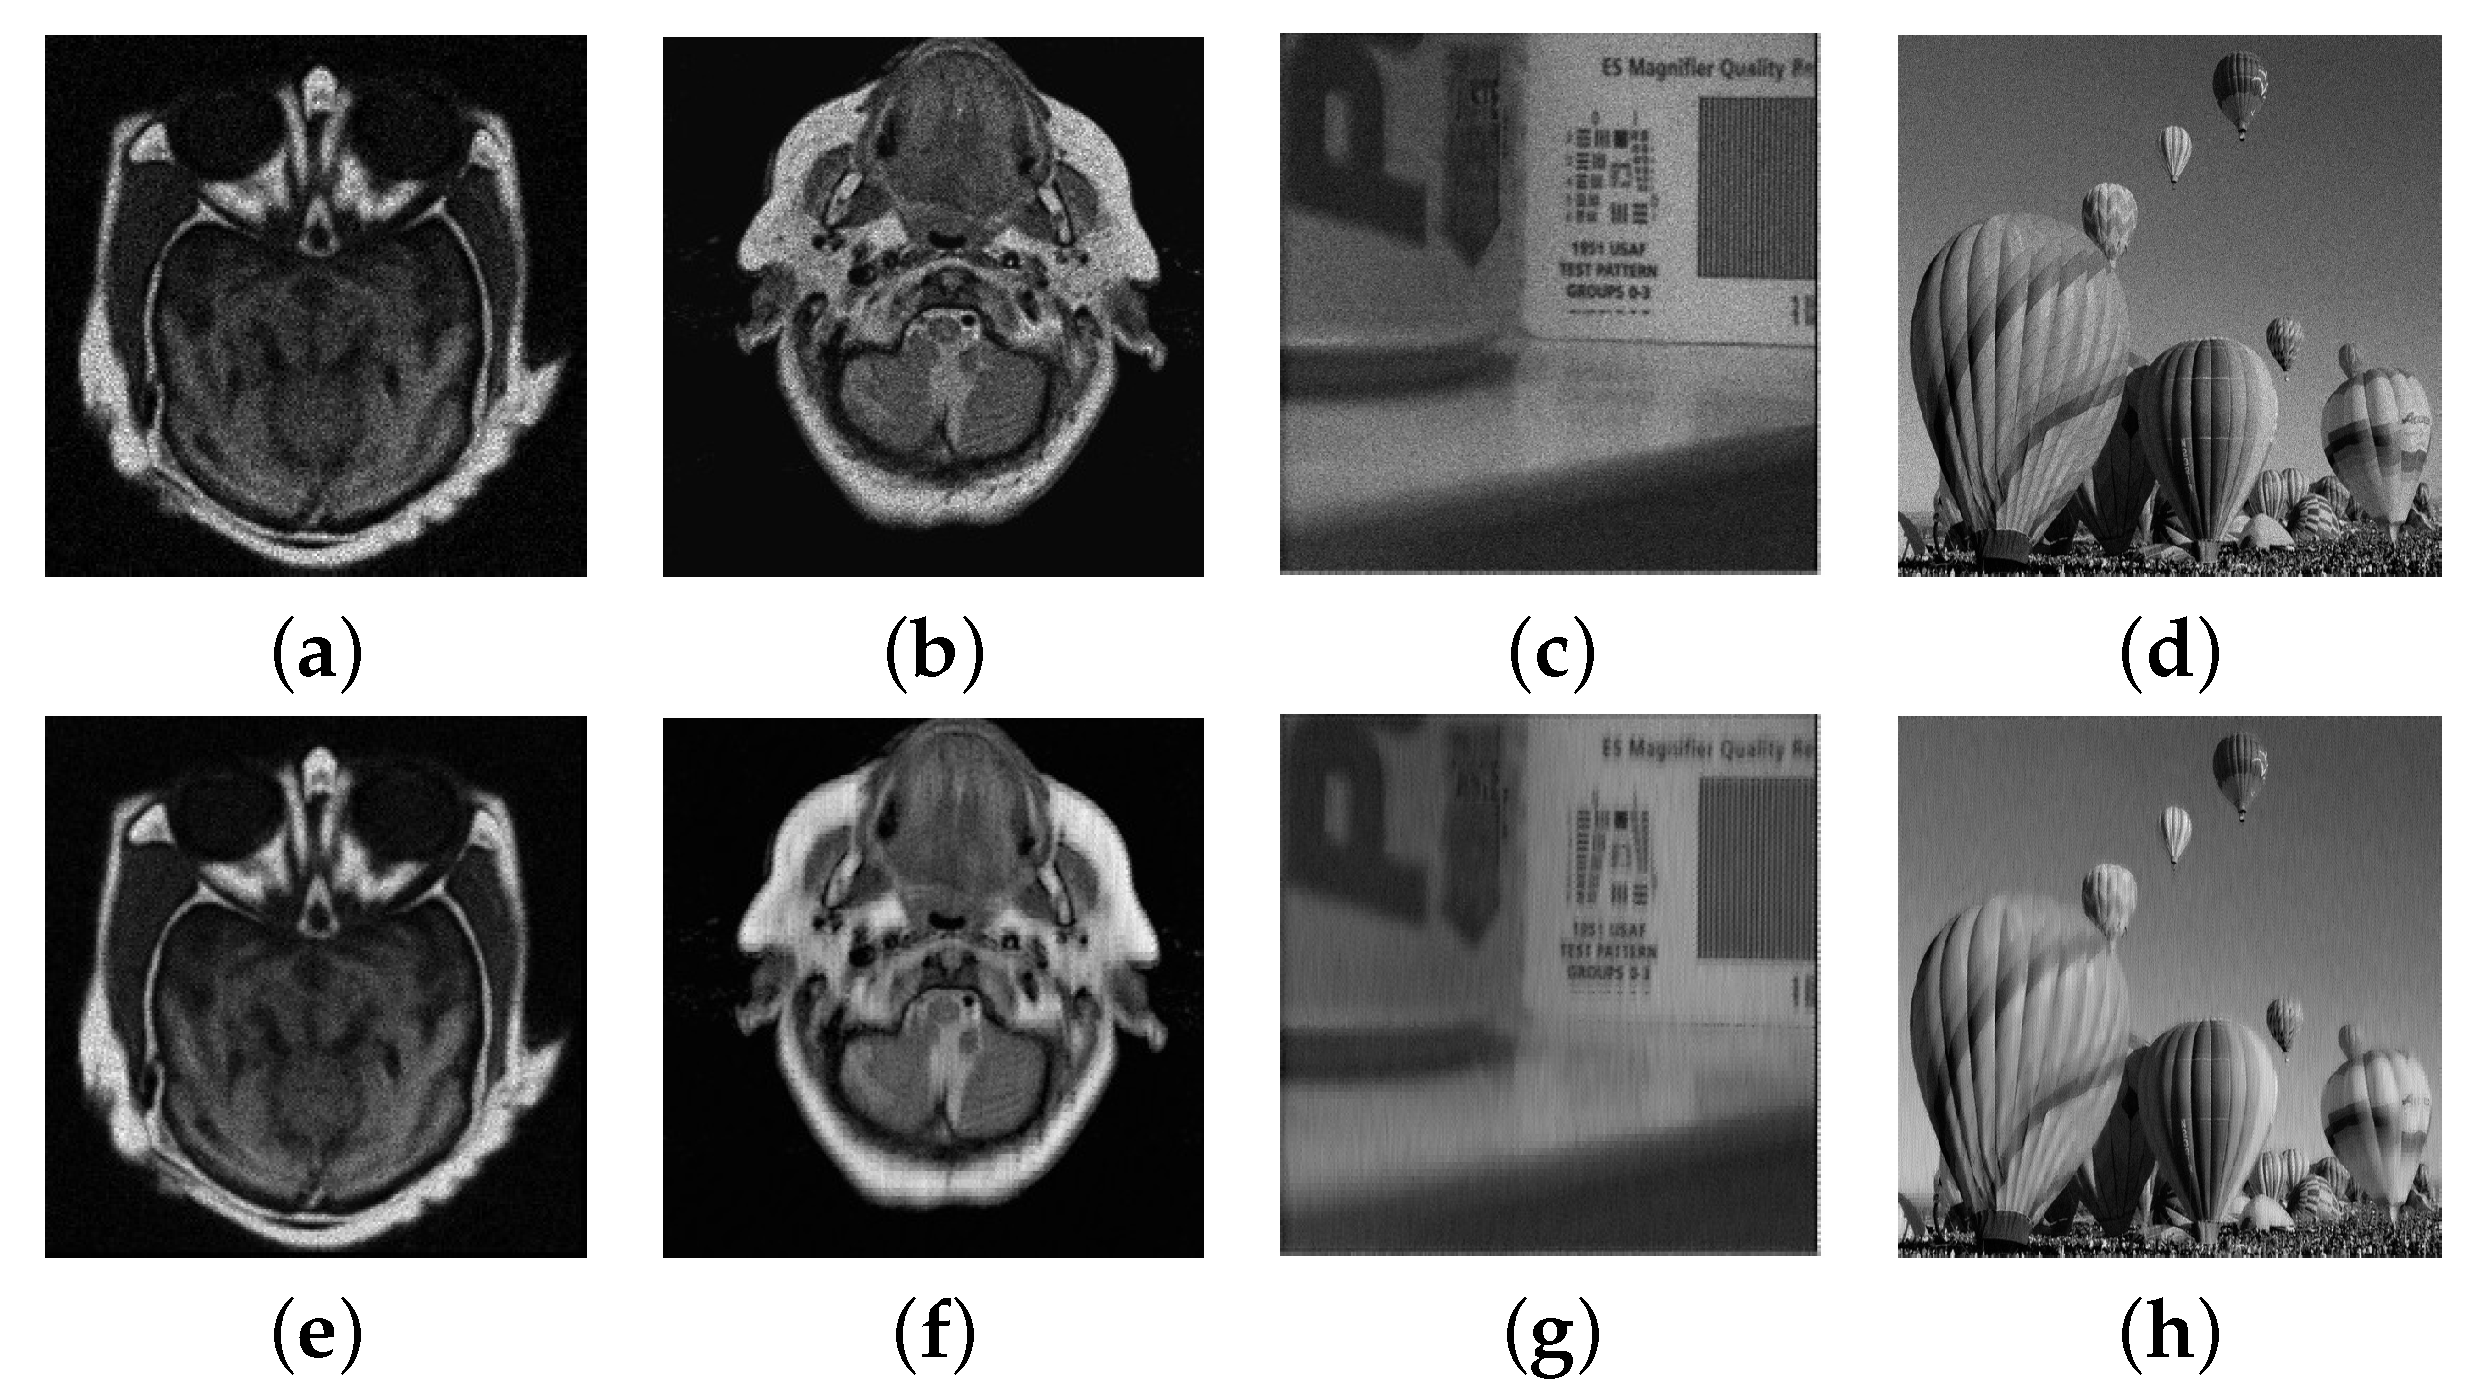

4.3. Numerical Experimental Results and Analysis